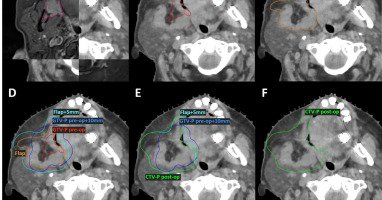

Since I was a #RadiationOncology resident, have always been "struggling" with consistency in target delineation for #postoperativeradiotherapy in #HeadNeckCancer such that I find my volumes "changing" over time! Kudos to @PierluigiBonomo @sueyom and team at @ESTRO_RT to work on

To date, no consensus guidelines have been published to guide the delineation of the primary and nodal Clinical Target Volumes (CTVs) in patients requiring post-operative radiotherapy (PORT) for...